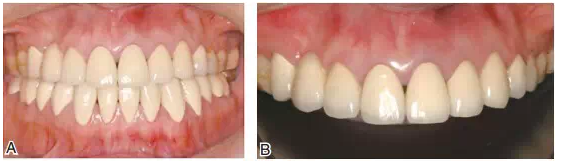

圖15下頜基牙初預(yù)備,在口內(nèi)確定垂直距離,采取硅橡膠頜位關(guān)系記錄。將上頜通過面弓轉(zhuǎn)移上牙合架,確定上頜和顳下頜關(guān)節(jié)的關(guān)系,再通過頜位關(guān)系記錄,對(duì)合上下頜模型上牙合架

圖19患者修復(fù)完成后的正面像及牙合曲線